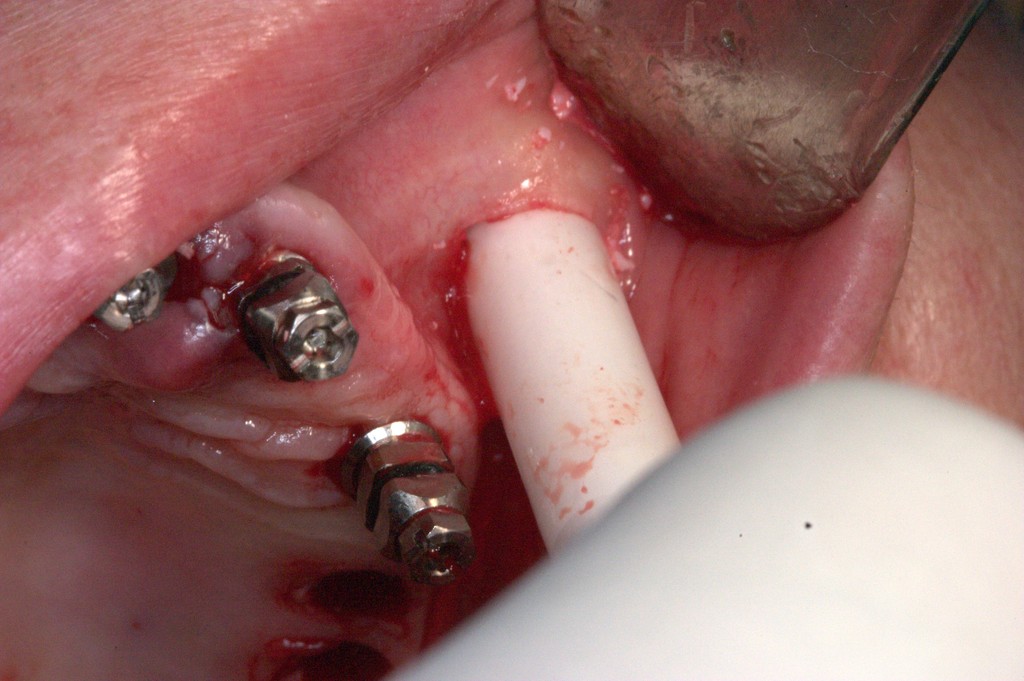

REHABILITACIÓN CON IMPLANTES ,ENFERMEDAD PERIODONTAL AVANZADA.

REHABILITACIÓN IMPLANTOSORTADA EN MANDÍBULA Y MAXILAR.